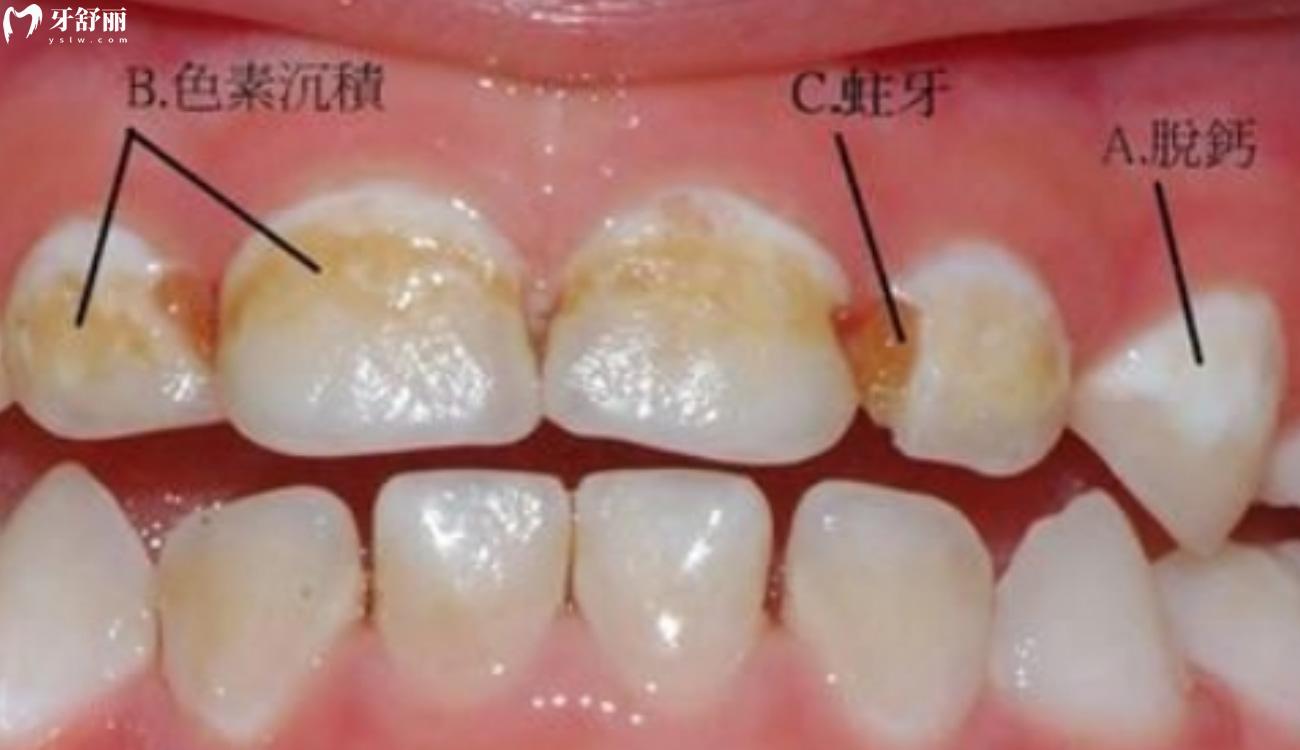

小编发现许多牙友分不清蛀牙和色素沉着,其实这两种的区别是比较大的,蛀牙的形成是由细菌代谢产生酸性物质,而色素沉淀的形成多是长期喝茶、吸烟等导致牙齿着色,只要仔细清洁,对于牙齿是没有伤害的。但蛀牙就不一样的,发现蛀牙要尽快进行补牙,不然发蛀牙会持续发展,伤害牙齿。

色素沉着和龋齿的区别

色素沉着和龋齿的本质区别是色素沉着对于牙齿本身没有伤害,而龋齿对于牙齿是有伤害的。

色素沉着是进食咖啡、浓茶等易引起色素沉着的食物、接触较多的铁、硫等矿物质,日常不注意口腔卫生习惯等因素导致牙齿着色。